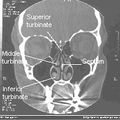

يقسم جوف الأنف بواسطة حاجز الأنف إلى قسمين أيمن وأيسر، ويقسم كل منهما بواسطة المحارات الأنفية الثلاثة إلى أربع فسحات هي من الأعلى للأسفل:

- الردب الوتدي الغربالي: يقع فوق المحارة الأنفية العلوية وخلفها.

- الصماخ الأنفي العلوي: يقع تحت المحارة العلوية ووحشيها.

- الصماخ الأنفي الأوسط: يقع تحت المحارة الأنفية الوسطى ووحشيها.

- الصماخ الأنفي السفلي: يقع تحت المحارة الأنفية السفلية ووحشيها.[1]